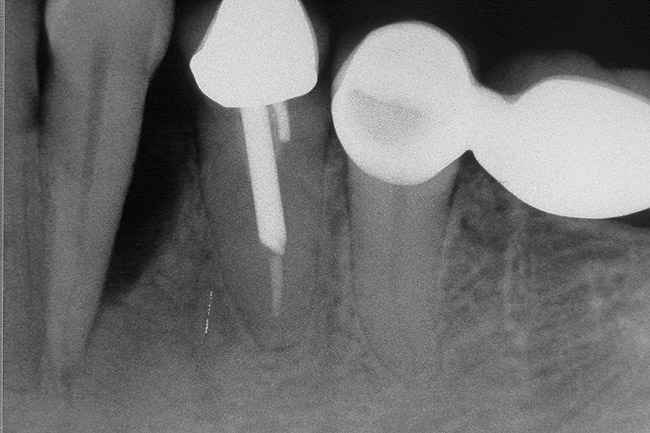

Figure 9 shows the implant placement at the time of extraction and Figure 10 shows the implant-supported fixed bridge. In one surgical procedure, the implants in the Nos. 29 and 31 positions were placed at the time of the extraction of these two teeth. The implants were restored approximately 3 months after placement.

Figure 9  Extraction of teeth Nos. 29 and 31 with immediate implants (Straumann USA, Waltham, MA) placed into the site.

Figure 9

Figure 10  Implants seen in Figure 9 restored approximately 3 months after placement.

Figure 10